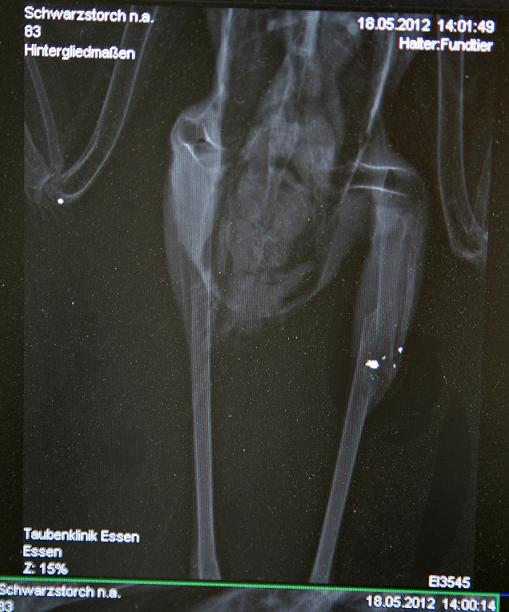

Lüdenscheid (NRW): Unbekannte schießen Schwarzstorch ab

Bild: Komitee gegen den Vogelmord